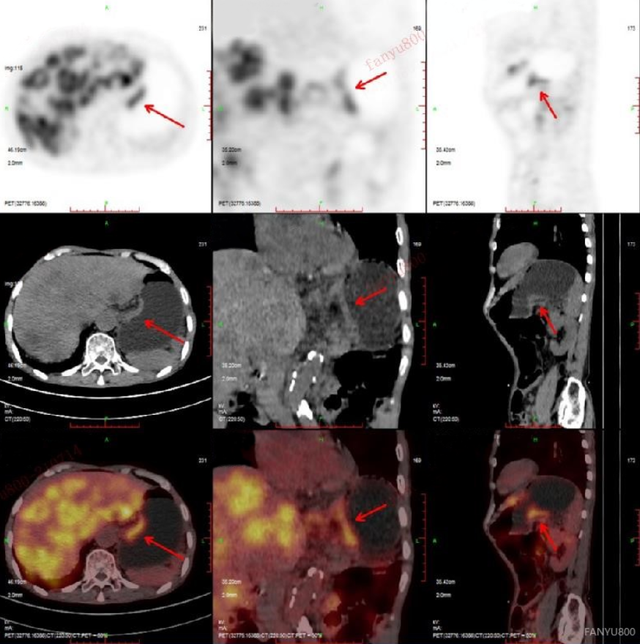

发布高建英主任petct在肿瘤远处转移中的临床应用